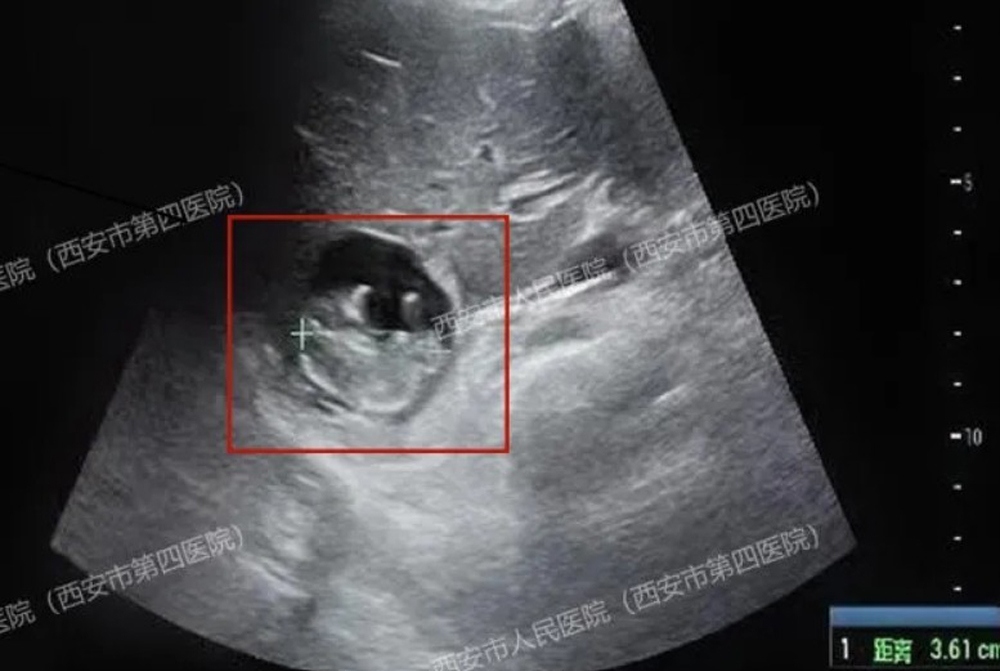

Trong lúc siêu âm, các bác sĩ ngạc nhiên khi phát hiện túi thai nằm trên bề mặt gan của người phụ nữ, một tình trạng cực kỳ hiếm gặp được gọi là "thai gan".

Một phụ nữ 40 tuổi họ Vương ở Tây An, tỉnh Thiểm Tây, Trung Quốc, gần đây đã đến bệnh viện để kiểm tra sau khi bị mất kinh 50 ngày. Xét nghiệm máu xác nhận cô đã mang thai. Tuy nhiên, kết quả siêu âm sau đó cho thấy không có túi thai trong tử cung hay ống dẫn trứng. Đội ngũ y tế tiếp tục điều tra và ngạc nhiên khi phát hiện túi thai nằm trên bề mặt gan của người phụ nữ, một tình trạng cực kỳ hiếm gặp được gọi là "thai gan", một loại thai ngoài tử cung nguy cơ cao và hiếm gặp.

Bác sĩ bất ngờ khi phát hiện thai nhi đang lớn lên trên gan. Ảnh: Qidian News.